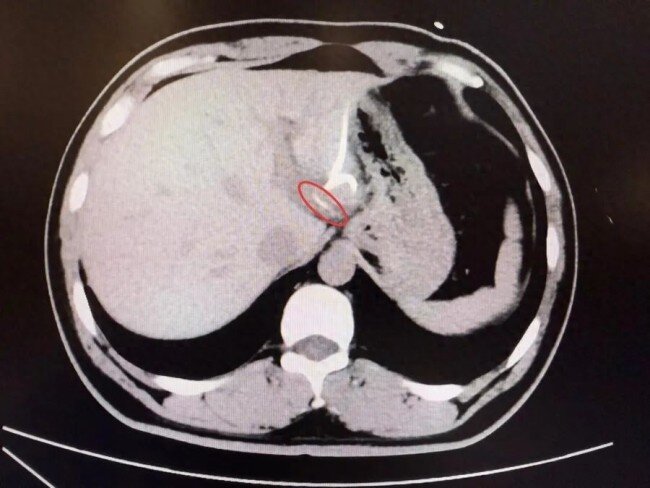

直到进行CT检查时,医生才惊讶地发现——肝脏左叶靠近胃贲门处,竟有一条细长的高密度影,形似鱼刺。原来,那根鱼刺在吞咽后穿透了胃壁,从贲门区域“钻”入肝脏,引发感染与脓肿。在简单进行肝脓肿介入穿刺引流后,当地外科医生评估后认为,要彻底清除异物,需要进行左半肝切除手术,但这对于李先生来说,创伤大、风险高,他难以接受。

为寻求更精准、微创的治疗,经当地内镜医生介绍后李先生辗转来到复旦大学附属中山医院内镜中心。“鱼刺位置非常凶险,就在贲门旁刺入左肝,紧贴大血管。”接诊的周平红主任介绍,“病程长、腹腔感染粘连严重,术中可能找不到鱼刺,一旦操作不慎也会造成内镜下无法控制的大出血。”周主任提出了个大胆的设想——能否通过胃镜,在食道管壁夹层建个隧道“开一扇门”,直接进入腹腔取出鱼刺?这个想法意味着要让内镜“跨越”胃壁的天然边界,是一次前所未有的尝试。术前,周平红主任带领内镜团队按照术前CT检查,反复推演每一步操作路径,力求安全与精准兼顾,在手术开始前由团队蔡明琰副主任医师进行超声内镜精准定位,为建立黏膜下隧道指明方向。